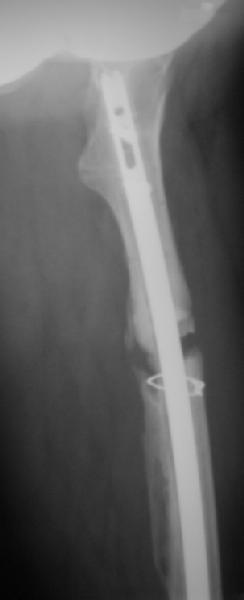

фото несращения бедра